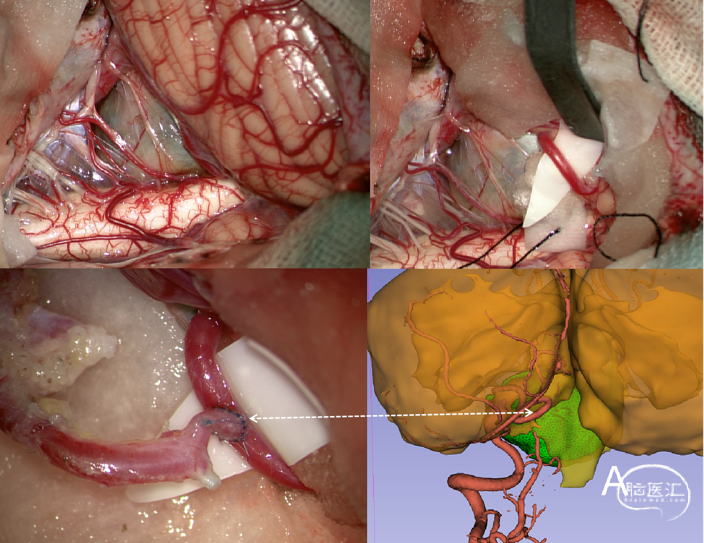

切口设计:拐杖性切口,“half-half”基础远外侧&枕下后正中入路,兼顾动脉瘤充分显露及搭桥PICA受体的选择(备选PICA-PICA侧侧吻合),皮瓣内标记枕动脉(OA)走行。

肌皮瓣一体下翻,显露C1、枕骨嶙部、乳突后部及枕髁内侧。

“内取”法分离枕动脉(inside-out技术),减少肌肉分层取OA的创伤。

OA-PICA搭桥后,试行近端阻断椎动脉,若对侧椎动脉返血明显,瘤体张力仍高,则行一期介入弹簧圈栓塞孤立,增加手术安全,减少创伤。